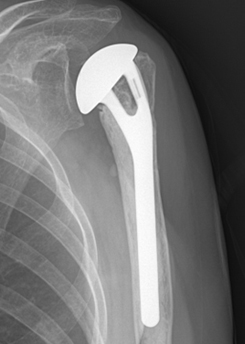

전이성 골절은 그대로 놔두면 어긋난 상태로 붙거나 잘 붙지 않을 가능성이 높습니다. 특히 근위 상완골에 붙어 있는 근육 기능이 감소하여 기능적으로 불편함이 남습니다. 따라서 많은 경우에 골편을 맞추는 수술이 필요합니다. 수술 방법으로는 골절부를 절개하는 방법과 절개하지 않고 맞추는 방법이 있습니다.골절부를 고정하는 방법으로는 핀, 쇠판, 철사 및 골수강내 정 등을 이용합니다. 간혹 골편이 4개로 분리된 심한 경우의 노인성 골절은 인공 관절 치환술을 시행하는 경우도 있습니다. 수술 방법은 골절부위를 노출시켜 어긋난 뼈를 맞추고 금속판이나 나사못으로 고정하는 방법이 널리 사용되고 있습니다. 그 외에도 골수강내핀고정법이 이용되기도 합니다.

노인에서 4분 골절이 발생되면

부러진 부분을인공 관절로 치환하는 수술이

적응이 되기도 합니다.

노인에서 4분 골절이 발생되면 부러진 부분을인공 관절로 치환하는 수술이 적응이 되기도 합니다.